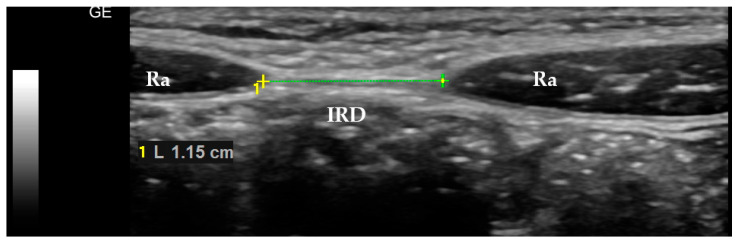

目的:本研究旨在评估儿童腹直肌转移的存在与可能归因于较宽白线的临床变量之间的关系。方法:对51例8 ~ 12岁儿童进行评价。研究方案包括超声测量白线宽度,人体测量,使用Tanita身体成分分析仪评估身体成分,以及评估临床病史和身体活动水平的问卷。结果:统计分析显示,直肌距离≥20mm在男孩、出生体长较高、腰臀比较高的儿童以及有先天性脐疝病史的儿童中更为常见。其他变量,如体力活动水平、体重、身体分析仪测量的身体成分参数、腹部症状(腹痛、便秘、尿失禁)的存在或肌肉骨骼疾病的家族史,与腹直肌转移的存在无关。结论:我们的研究结果提示儿童腹直肌转移的先天性背景,特别是考虑到其在男孩和那些出生时具有特定身体参数的儿童中的患病率较高。

Objectives: This study was aimed at the assessment of the relationship between the presence of diastasis recti abdominis in children and the clinical variables potentially attributable to the wider linea alba. Methods: Fifty-one children, aged 8-12 years, were evaluated. The study protocol included ultrasonographic measurements of the linea alba width, anthropometric measurements, body composition assessment with the use of the Tanita Body Composition Analyzer, and the questionnaire assessing clinical history and the level of physical activity. Results: Statistical analysis revealed that the interrectus distance, which was ≥20 mm, was significantly more often found in boys, in children with a higher body length at birth and a higher waist/hip ratio, and also in those with a history of congenital umbilical hernia. Other variables, such as the level of physical activity, body weight, parameters of the body composition measured with the body analyzer, presence of abdominal symptoms (abdominal pain, constipation, urinary incontinence), or family history of musculoskeletal disease, were not associated with the presence of diastasis recti abdominis. Conclusions: The results of our study suggest a congenital background of diastasis recti abdominis in children, especially given its higher prevalence among boys and those children who presented with specific body parameters at birth.